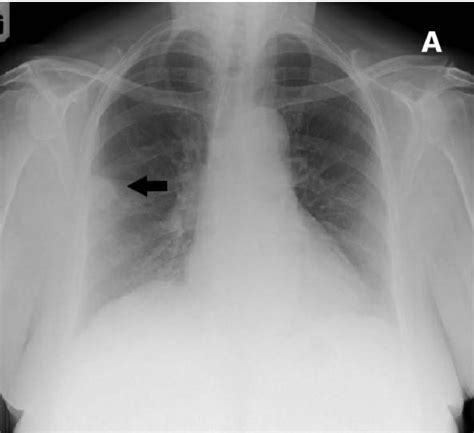

Key findings on a Pulmonary Embolism X Ray that may suggest PE include:

• Wedge-shaped opacities: These are areas of increased density in the lung tissue, often seen in the periphery of the lung.

• Pleural effusion: Fluid accumulation in the pleural space, which can be a sign of inflammation or infection.

• Enlarged pulmonary arteries: Dilatation of the pulmonary arteries, which may indicate increased pressure due to a clot.

• Atelectasis: Collapse or incomplete expansion of the lung tissue, which can be a sign of obstruction.

However, it is important to note that these findings are not specific to PE and can be seen in other conditions. Therefore, further diagnostic testing is often required to confirm the diagnosis.